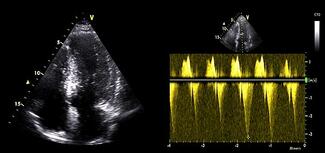

Burcu Kodal, MD; Tahir Bezgin, MD; Aziz Inan Celik, MD

A 58-year-old man presented to the emergency department with chest pain consistent with angina. Electrocardiography revealed no ischemic changes; however, serial troponin measurements showed a rising trend.